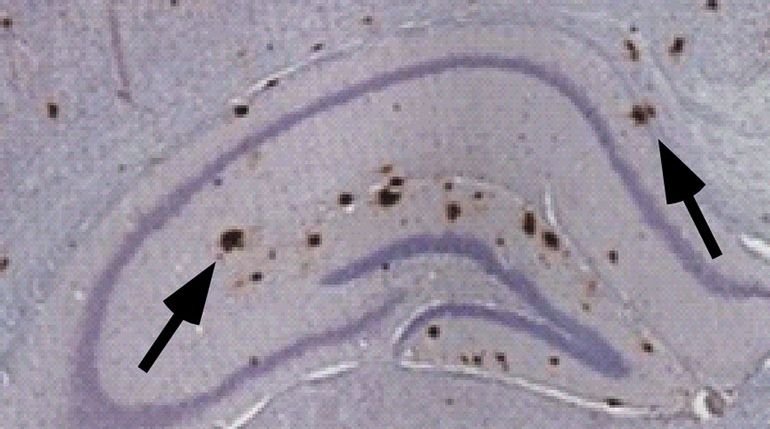

La carenza di vitamina A aumenta la produzione di placche (indicate dalle frecce) nel cervello dei topi. Fonte: University of BC

I ricercatori hanno scoperto che anche una leggera carenza di vitamina A aumenta la produzione di amiloide-beta, la proteina che forma le placche che soffocano e infine uccidono i neuroni nell'Alzheimer. Egli ha anche scoperto che questi topi, quando privi di vitamina A, da adulti ottengono risultati peggiori nel test standard di apprendimento e memoria.